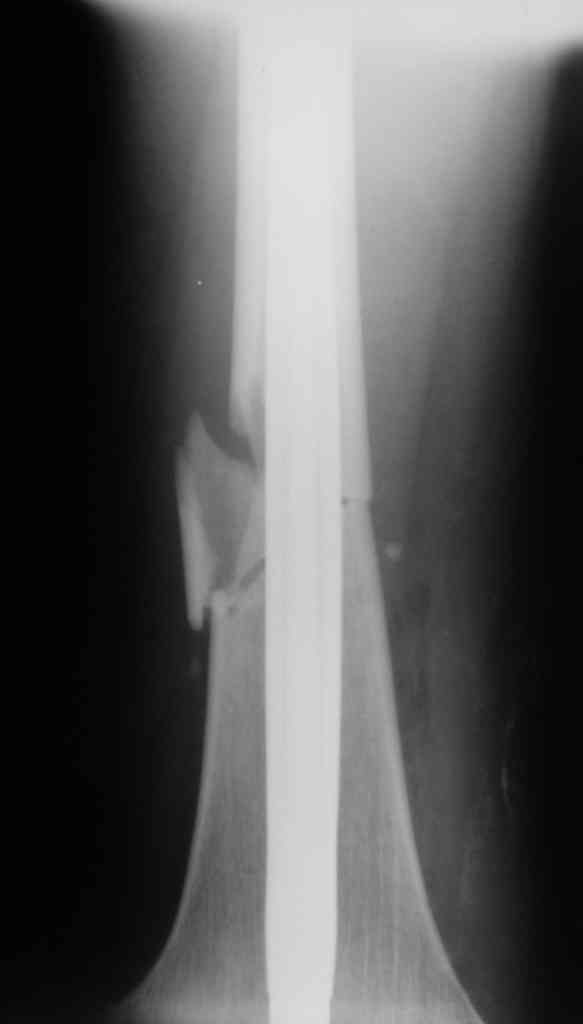

Дорогой Александр. Имею скромный опыт использования системы Fixion при

переломах плеча, бедра и тибии. Всего 18 наблюдений с сентября 2007

г.Результаты отличные. Гвоздь индивидуален для каждого медулярного

канала. Легко имплантируется как в узкий, так и в деформированный

канал. Это позволяет применять метод интрамедулярного остеосинтеза без

ненужных потерь времени операции, флюороскопии и реально снижает

крвопотерю и операционный риск. Удаление происходит без проблем.

Особенно интересны больные с ипсилатеральными переломами бедра и голени.

В отношении ранней нагрузки при спиральных переломах лучше не

торопиться. По данному случаю необходимо достигнуть исчезновения щели

между штифтом и внутреним кортексом по Rg. А так картинка прекрасная -

и длина сегмента и репозиция. Можно поздравить, коллега!